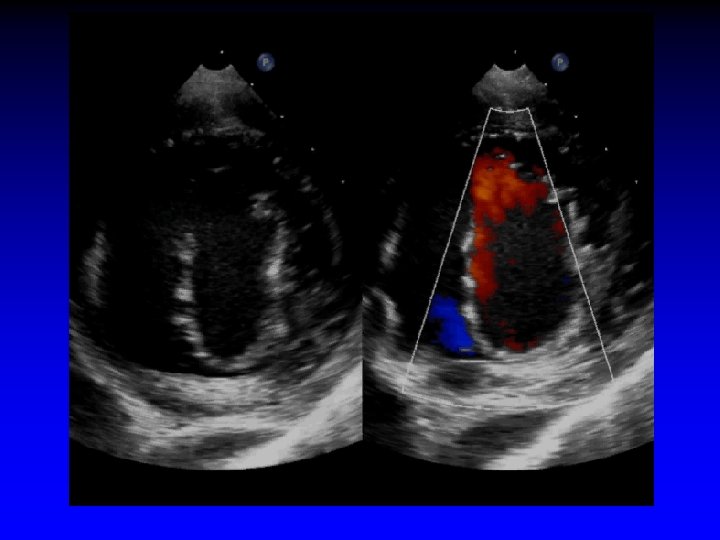

Case 1 Ruptured cords P 2

1. 6 cm +. . . + Gastric short-axis view (PSR view)